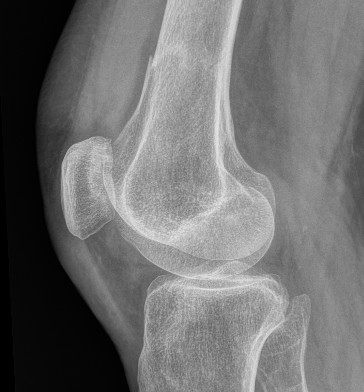

Xray

![]()

Lateral split fracture distal femur

Xray / CT